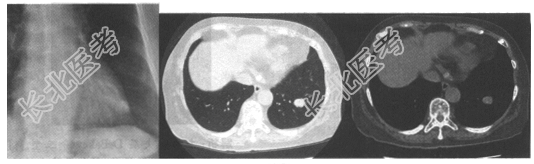

- [材料题] 患者,女,35岁。咳嗽1个月余,胸片及CT如下图。

- 简答题1、针对上述病例,请问哪种疾病可能性最大?

- 简答题2、为进一步确诊,可选择哪些检查方法?

- 简答题3、请问有什么治疗方案?